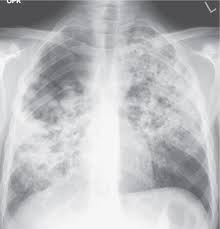

Airspace disease is considered chronic when it persists beyond 4-6 weeks after treatment. These fluffy opacities tend to be confluent meaning they blend into one another with imperceptible margins. Consolidation or ground-glass opacity occurs when alveolar air is replaced by fluid pus blood cells or other material.

Airspace disease can be acute or chronic and commonly present as consolidation or ground-glass opacity on chest imaging. Interstitial lung disease is an umbrella term that includes many different conditions. Occlusive vascular disease can be termed a mosaic perfusion pattern in this setting 7. The opacified acini become confluent producing a fluffy homogeneous radiographic pattern characteristic of airspace disease as seen in Fig. It is typically defined as an area of hazy opacification x-ray or increased attenuation CT due to air displacement by fluid airway collapse fibrosis or a neoplastic process. Some examples of COPD include asthma bronchitis and emphysema. Airspace disease can be acute or chronic and commonly present as consolidation or ground-glass opacity on chest imaging. It is by far the most common reason of the presence of air in lungs. Bronchiectasis cystic fibrosis constrictive bronchiolitis.